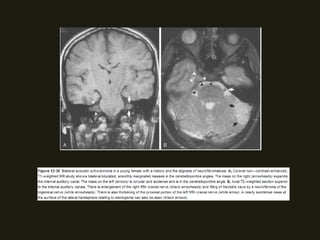

SCHWANOMAS ACÚSTICOS

• Tumores benignos do VIII PC ocorrem no CAI/ângulo

as de Schwann; Associação com neurofibromatose tipo 2;

• RM método de escolha (nervo espessado e com realce pelo

pequenos dos nervos normais;

• Podem ser massas pequenos ou grandes;

hidrocefalia e compressão do IV ventrículo;

acusticus e cápsula óptica; Assimetria dos CAI > 2mm sugere

NEOPLASIAS BENIGNAS SCHWANOMAS ACÚSTICOS • Tumores benignos do VIII PC ocorrem no CAI/ângulo cerebelopontino, surgindo na junção das células da glia com as de Schwann; Associação com neurofibromatose tipo 2; • Sintomas dependem da localização do tumor (há compressão dos nervos coclear e vestibular (CAI) – zumbido, diminuição acuidade auditiva; • RM método de escolha (nervo espessado e com realce pelo contraste; podem ser císticos;); diferencia schwanomas pequenos dos nervos normais;

NEOPLASIAS BENIGNAS • Podemser massas pequenos ou grandes; • Grandes – distorção da fossa posterior; hérnia de tronco, hidrocefalia e compressão do IV ventrículo; • TC alta resolução – mostras alterações ósseas do CAI, porus acusticus e cápsula óptica; Assimetria dos CAI > 2mm sugere MASSA!!